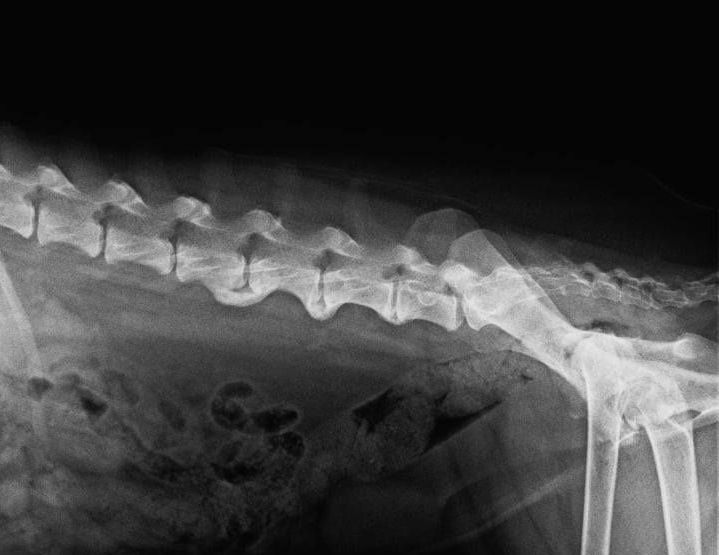

Der Tierarzt kann den Kreuzbandriss durch den sogenannten Schubladen- oder den Tibiakompressionstest feststellen, sollte dies noch nicht zur vollständigen Klarheit führen, so müssen bilgebende Verfahren (Röntgen, CT, MRT) hinzugezogen werden.